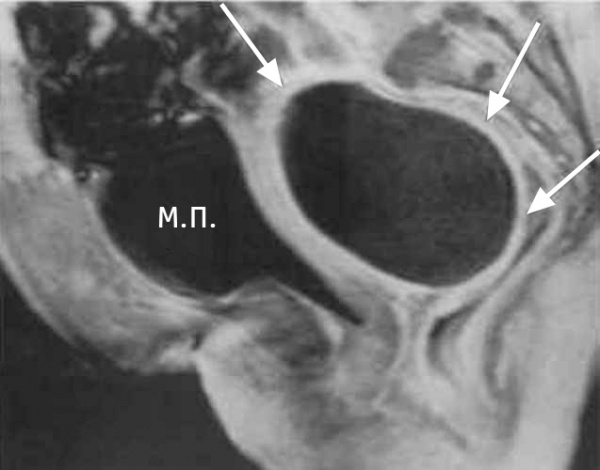

(Слева) Трансвагинальная уль трасонография в продольной плоскости; визуализируется расширенная болезненная фаллопиева труба, содержащая низкоуровневые эхосигналы и неполную перегородку. Такие признаки характерны для пиосальпинкса.

(Справа) MPT, Т2, TSE, сагиттальный срез у этой же пациентки; определяется уровень детрита в пиосальпинксе. Бесчисленные крупные фиброиды было трудно оценить при ультрасонографии.